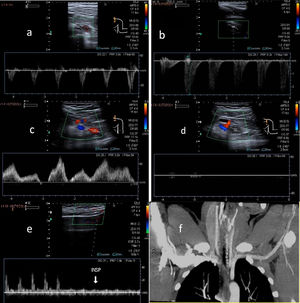

La ecografía Doppler se usa como método de cribado, al ser no invasiva y no emitir radiaciones. El estudio de la AP comienza por encima de la articulación de la rodilla hasta que se bifurca y de manera bilateral. El estudio se realiza con el paciente en decúbito prono, con la pierna extendida y en posición neutral para establecer los cambios de la capa íntima del vaso, la presencia de estenosis o aneurismas, así como la velocidad y la morfología de la curva espectral16,18. La segunda parte del estudio consiste en las maniobras de estrés, en las que el tobillo se coloca en dorsiflexión y flexión plantar hasta 30 segundos, donde el radiólogo puede ayudar a mantener la postura mediante presión (fig. 9 A). Posteriormente, el paciente se pondrá en bipedestación, sobre la punta de los pies15,16. Durante este momento evaluaremos el flujo en todo el recorrido de la AP y evaluaremos la presencia o ausencia del flujo y la disminución del pico sistólico con las maniobras de estrés (fig. 9 B). También podremos evaluar la arteria pedia y la arteria tibial posterior17,19.

Maniobras de estrés para valoración del síndrome de atrapamiento poplíteo. Paciente en decúbito prono, con la pierna extendida y el tobillo en dorsiflexión (A) y extensión plantar (B) durante 30 segundos. El radiólogo puede ayudar a mantener la postura mediante presión. Se evaluará la presencia, ausencia o cambios en el flujo de todo el recorrido de la arteria poplítea con los cambios de posición. C y D muestran hallazgos normales en Doppler espectral con las maniobras de estrés de flexión y extensión.

La estenosis de la AP puede ser cuantificada midiendo la ratio de la Vps en la lesión: la Vps es medida en la estenosis y se compara con la arteria sana contralateral, creando una ratio específica para cada paciente. Radonic V et al. (2000) definieron que una ratio mayor de 2 sería una estenosis significativa.

El flujo turbulento con aliasing es necesario para detectar una estenosis hemodinámicamente significativa. Se considera que hay una obstrucción de los vasos si no se detecta flujo ni por Doppler color ni pulsado18 (fig. 10). Para visualizar las variantes anatómicas correctamente, podremos complementar el estudio con una angio-RM.